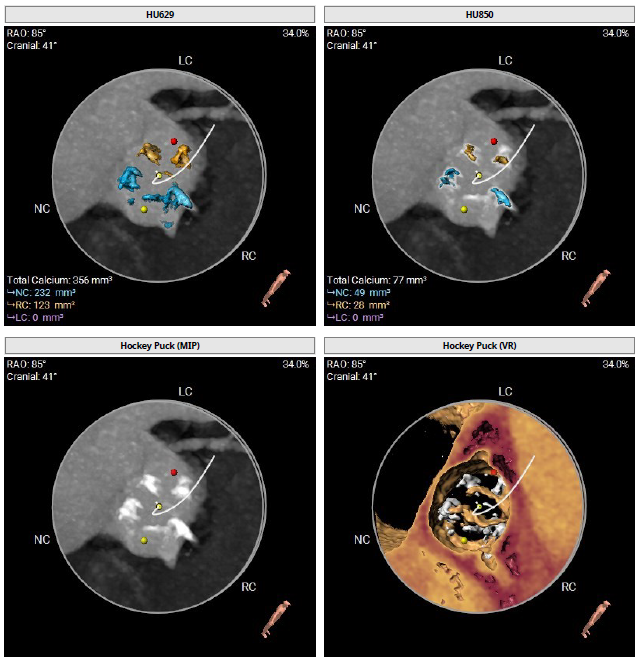

术前CT检查

该患者术前CT分析瓣环20.0mm,流出道22.0mm, Type0型二叶瓣,瓣叶轻中度钙化并增厚,瓣膜锚定力可,流出道直筒偏敞口,预估瓣膜释放后位移风险低,少量瓣周漏可能;